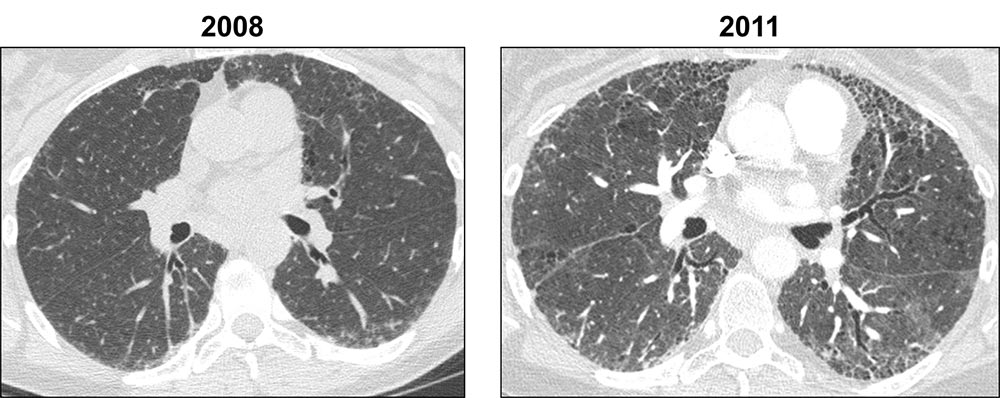

This series of axial HRCT images shows the progression of usual interstitial pneumonia (UIP) over time. The peripheral reticulation in the 2008 image has progressed to honeycombing over the 3 year time period, and prominent traction bronchiectasis is seen in the later image, a feature not seen previously.

Images courtesy of and used with permission from Sudhakar Pipavath, MD.